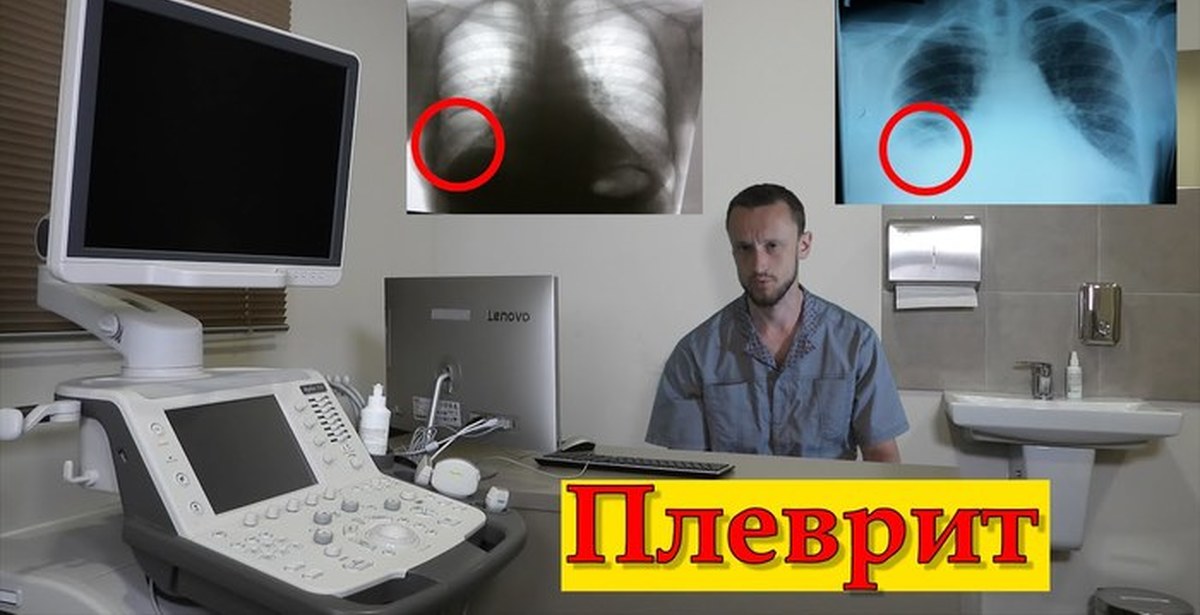

Диагностика плеврального выпота: что нужно знать